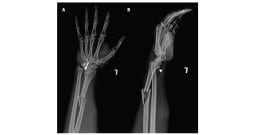

Eine harte Beule nach einem Sturz ist in der Regel unbedenklich und deutet nicht auf eine schwerwiegende Verletzung hin. Eine weiche, teigige Schwellung hingegen könnte auf einen Bruch oder Riss im Schädelknochen hindeuten – in diesem Fall sollte umgehend ein Arzt konsultiert werden. Eine Beule an der Stirn mit einer weichen Schwellung in der Mitte ist in der Regel harmlos. Trotzdem sollten solche Verletzungen beobachtet und im Zweifelsfall medizinisch abgeklärt werden.